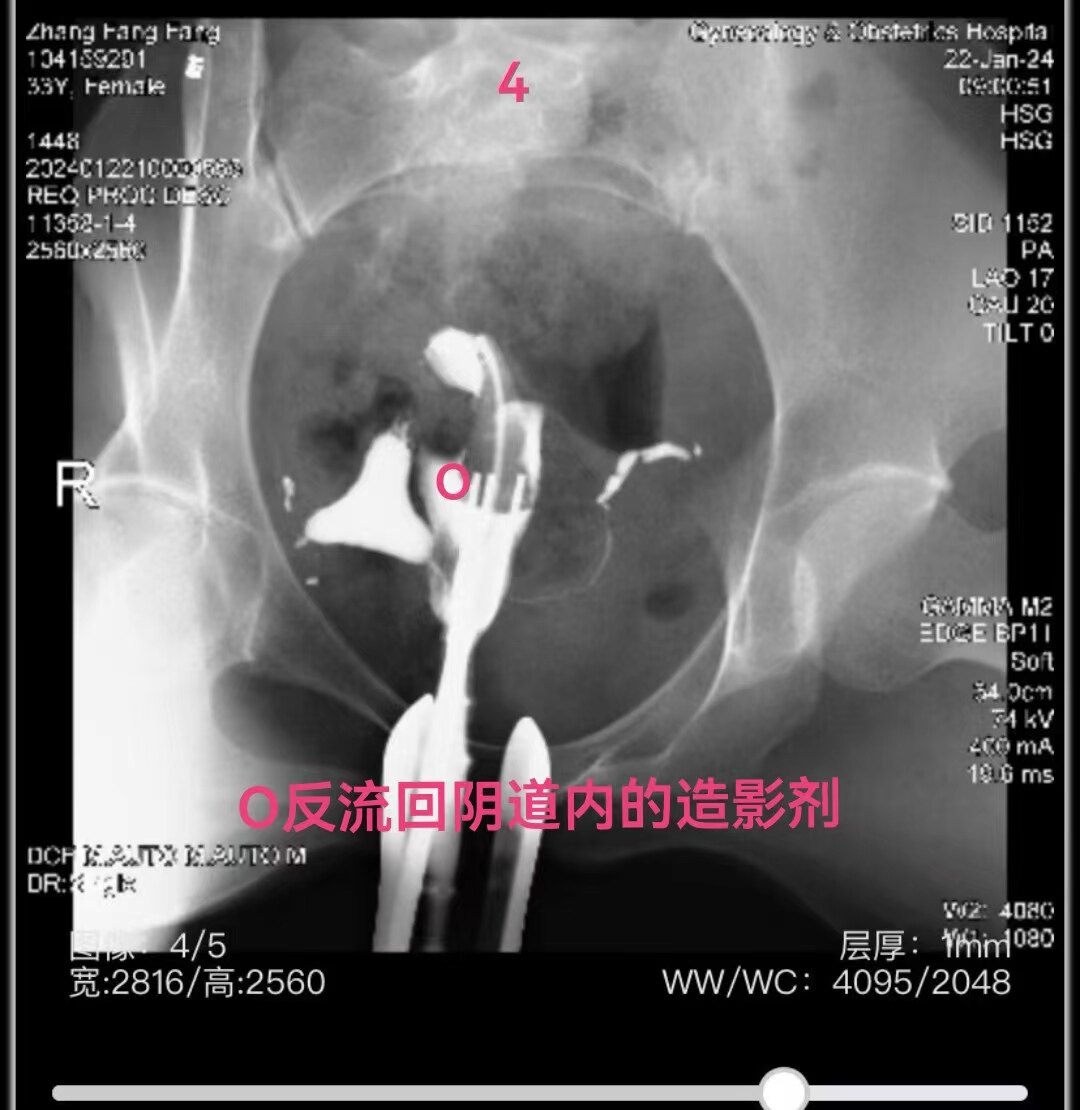

44.jpg

左侧输卵管显影至伞部,右侧输卵管显影至壶腹部近段。造影剂返回到阴道

4.jpg